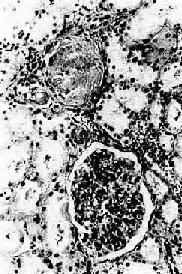

镜检下,肾细动脉硬化明显,小叶间动脉及弓形动脉内膜增厚。依病程而有多少不等的入球动脉及肾小球发生玻璃样变(图8-12)。附近的肾小管由于缺血而萎缩、消失,间质结缔组织增生及淋巴细胞浸润。该处由于肾实质萎缩和结缔组织收缩而形成凹陷的固缩病灶,周围健存的肾小球发生代偿性肥大,所属肾小管亦呈代偿性扩张,使局部肾组织向表面隆起,形成肉眼所见的无数红色细颗粒(由于该处血供良好而呈红色)。

图8-12 高血压病之肾

肾小球入球小动脉管壁玻璃样变性,肾小球纤维化,玻璃样变